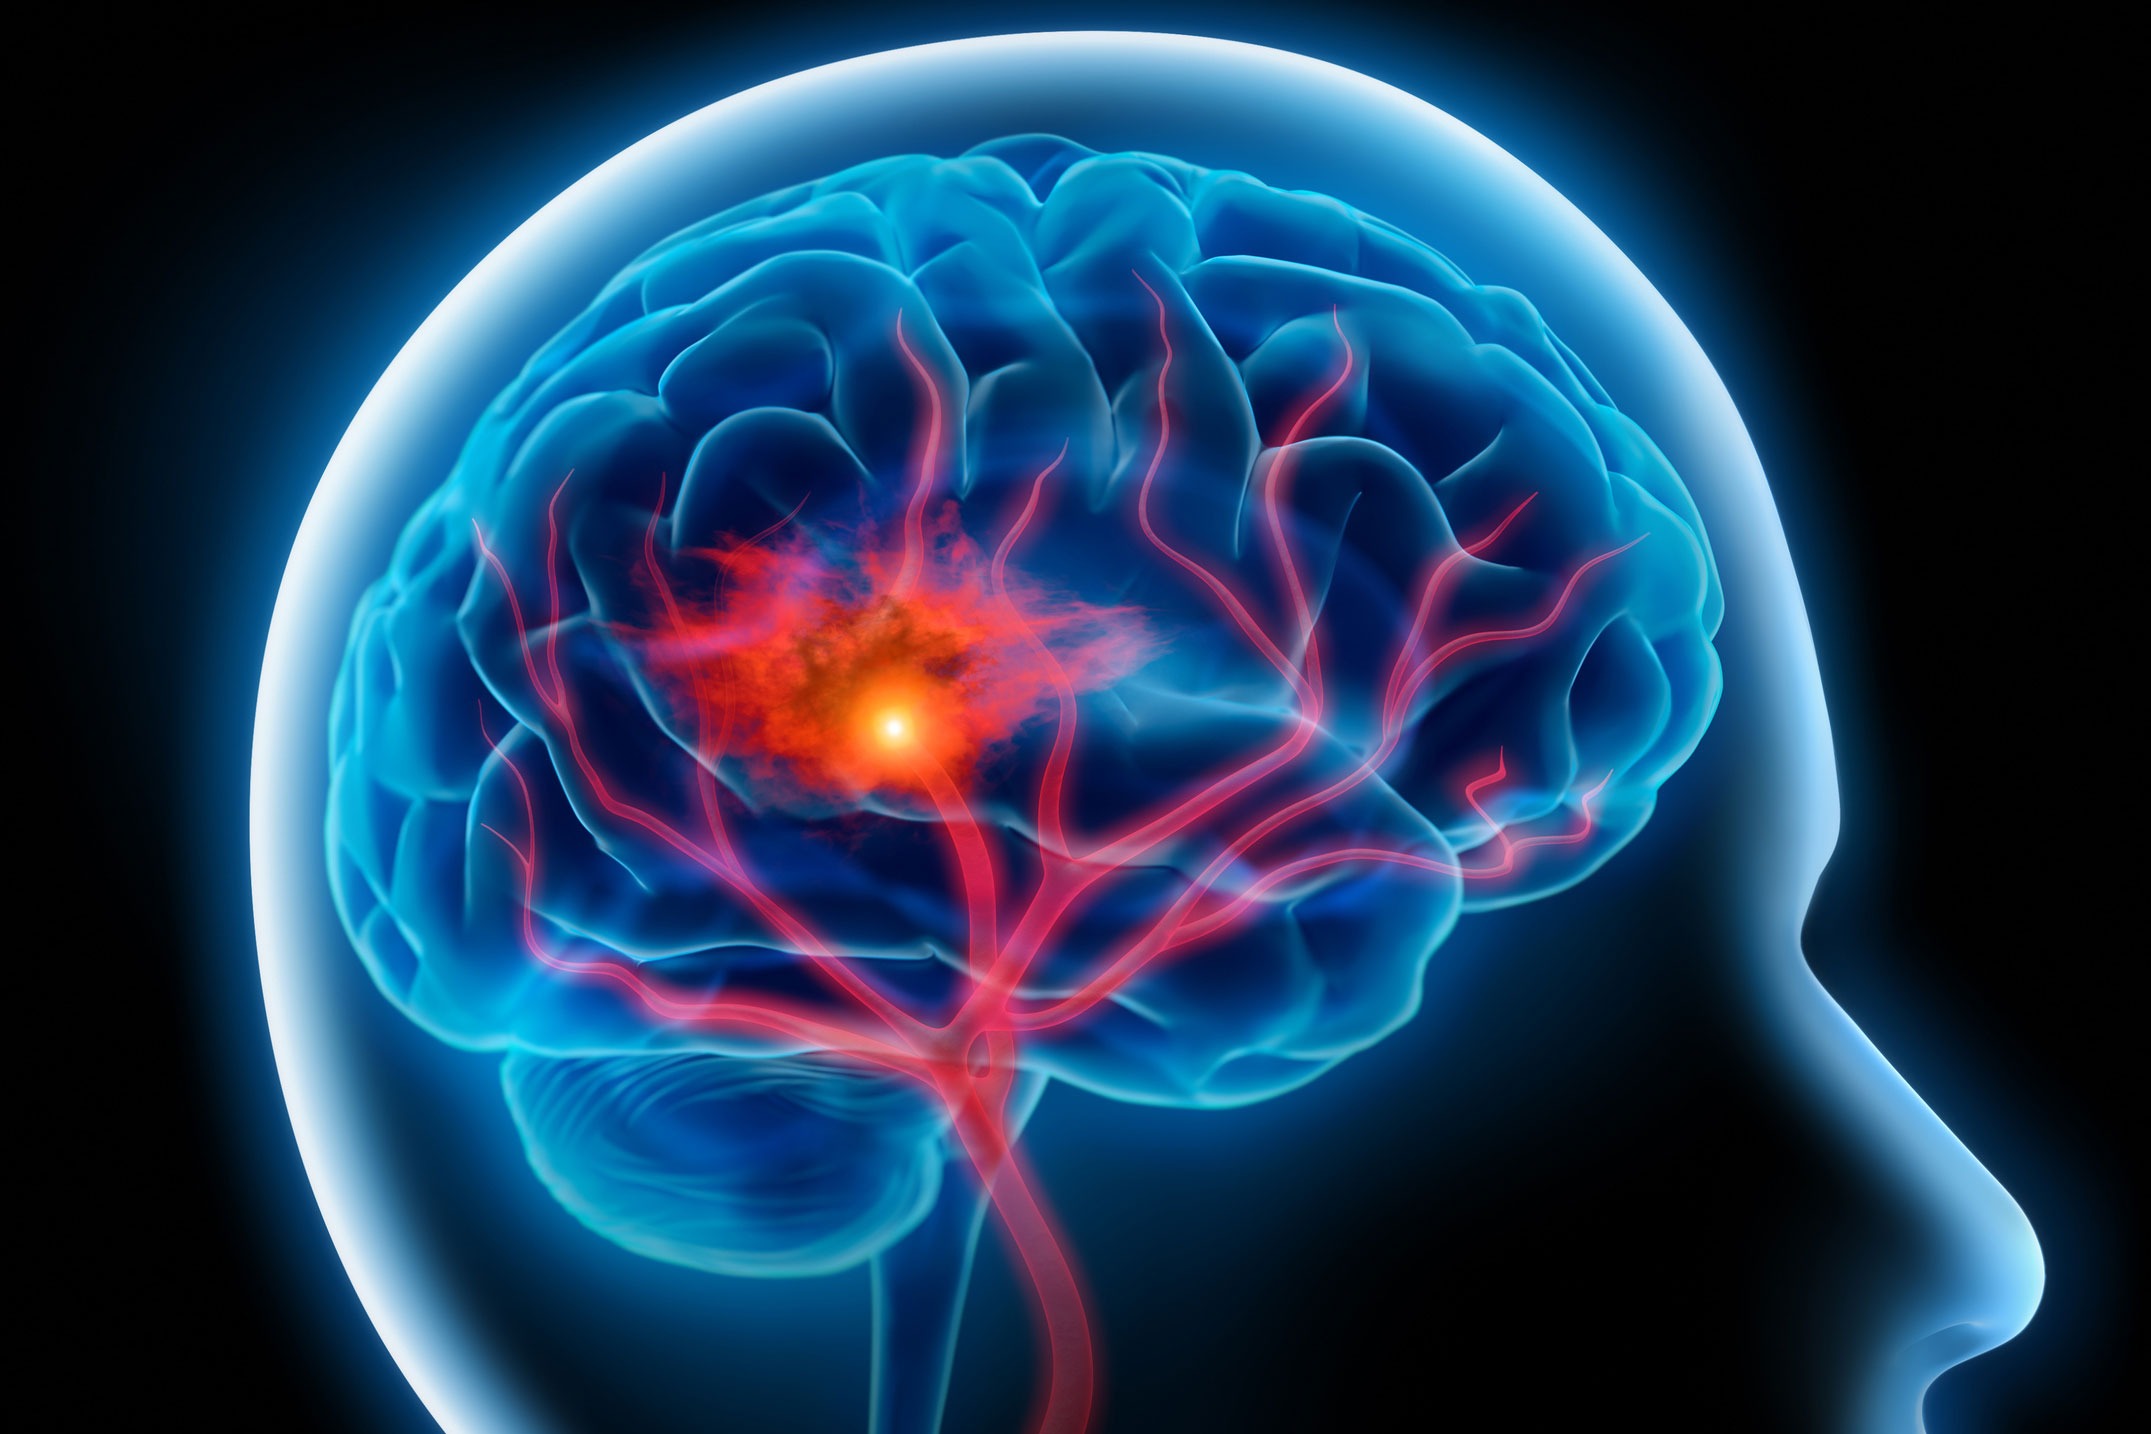

Ишемический инсульт левой стороны: симптомы и реабилитация